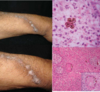

Diagnostico mediante hallazgo clinico y de cultivo

Mucormicosis por Cuningamella bertholatiae

Vesiculas con esterigmatas en forma de flor

Esporangiosporas